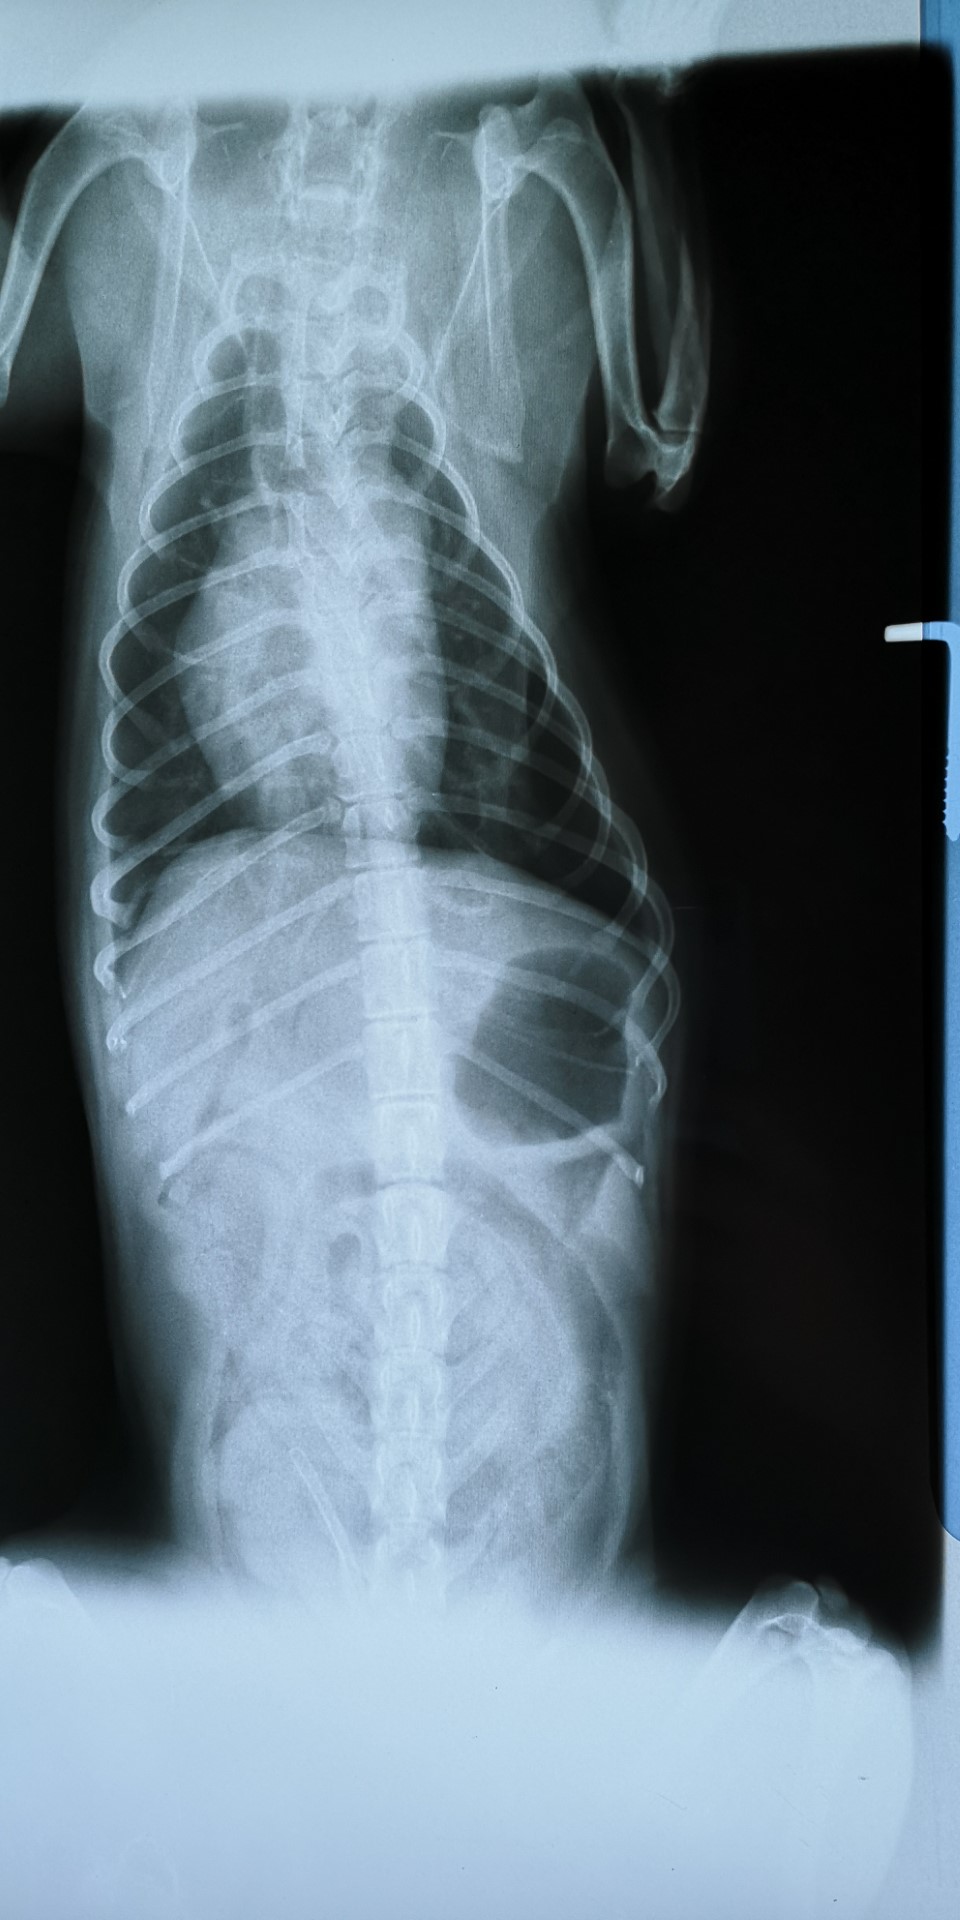

Animalia, veterinarska ambulanta za male živali, specialistični pregledi eksotičnih živali, ptic, ter glodalcev